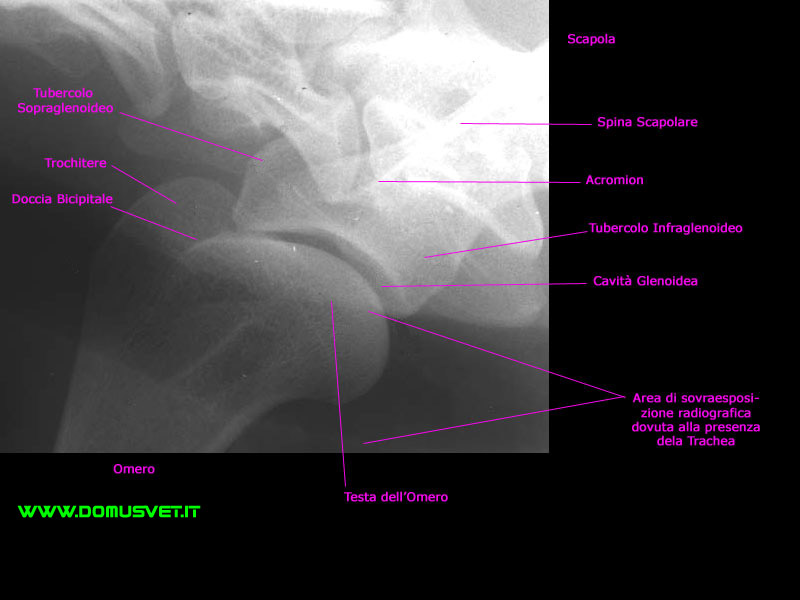

Atlante Radiografico del cane: Spalla LL

Spalla LL